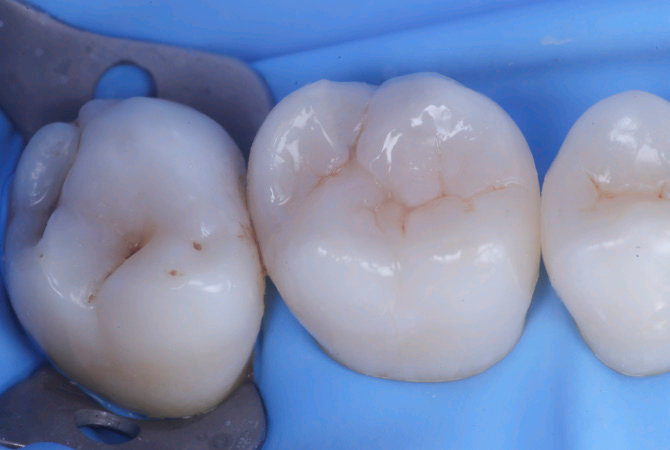

Fig.5 Aspetto della chiusura cervicale e sulle pareti assiali della seconda matriceFig.6 Aspetto occlusale delle pareti interprossimali appena create

7